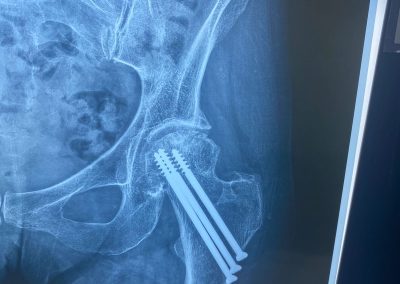

تم إجراء تثبيت داخلي لكسر بالحوض بمسامير عام ٢٠٠٩